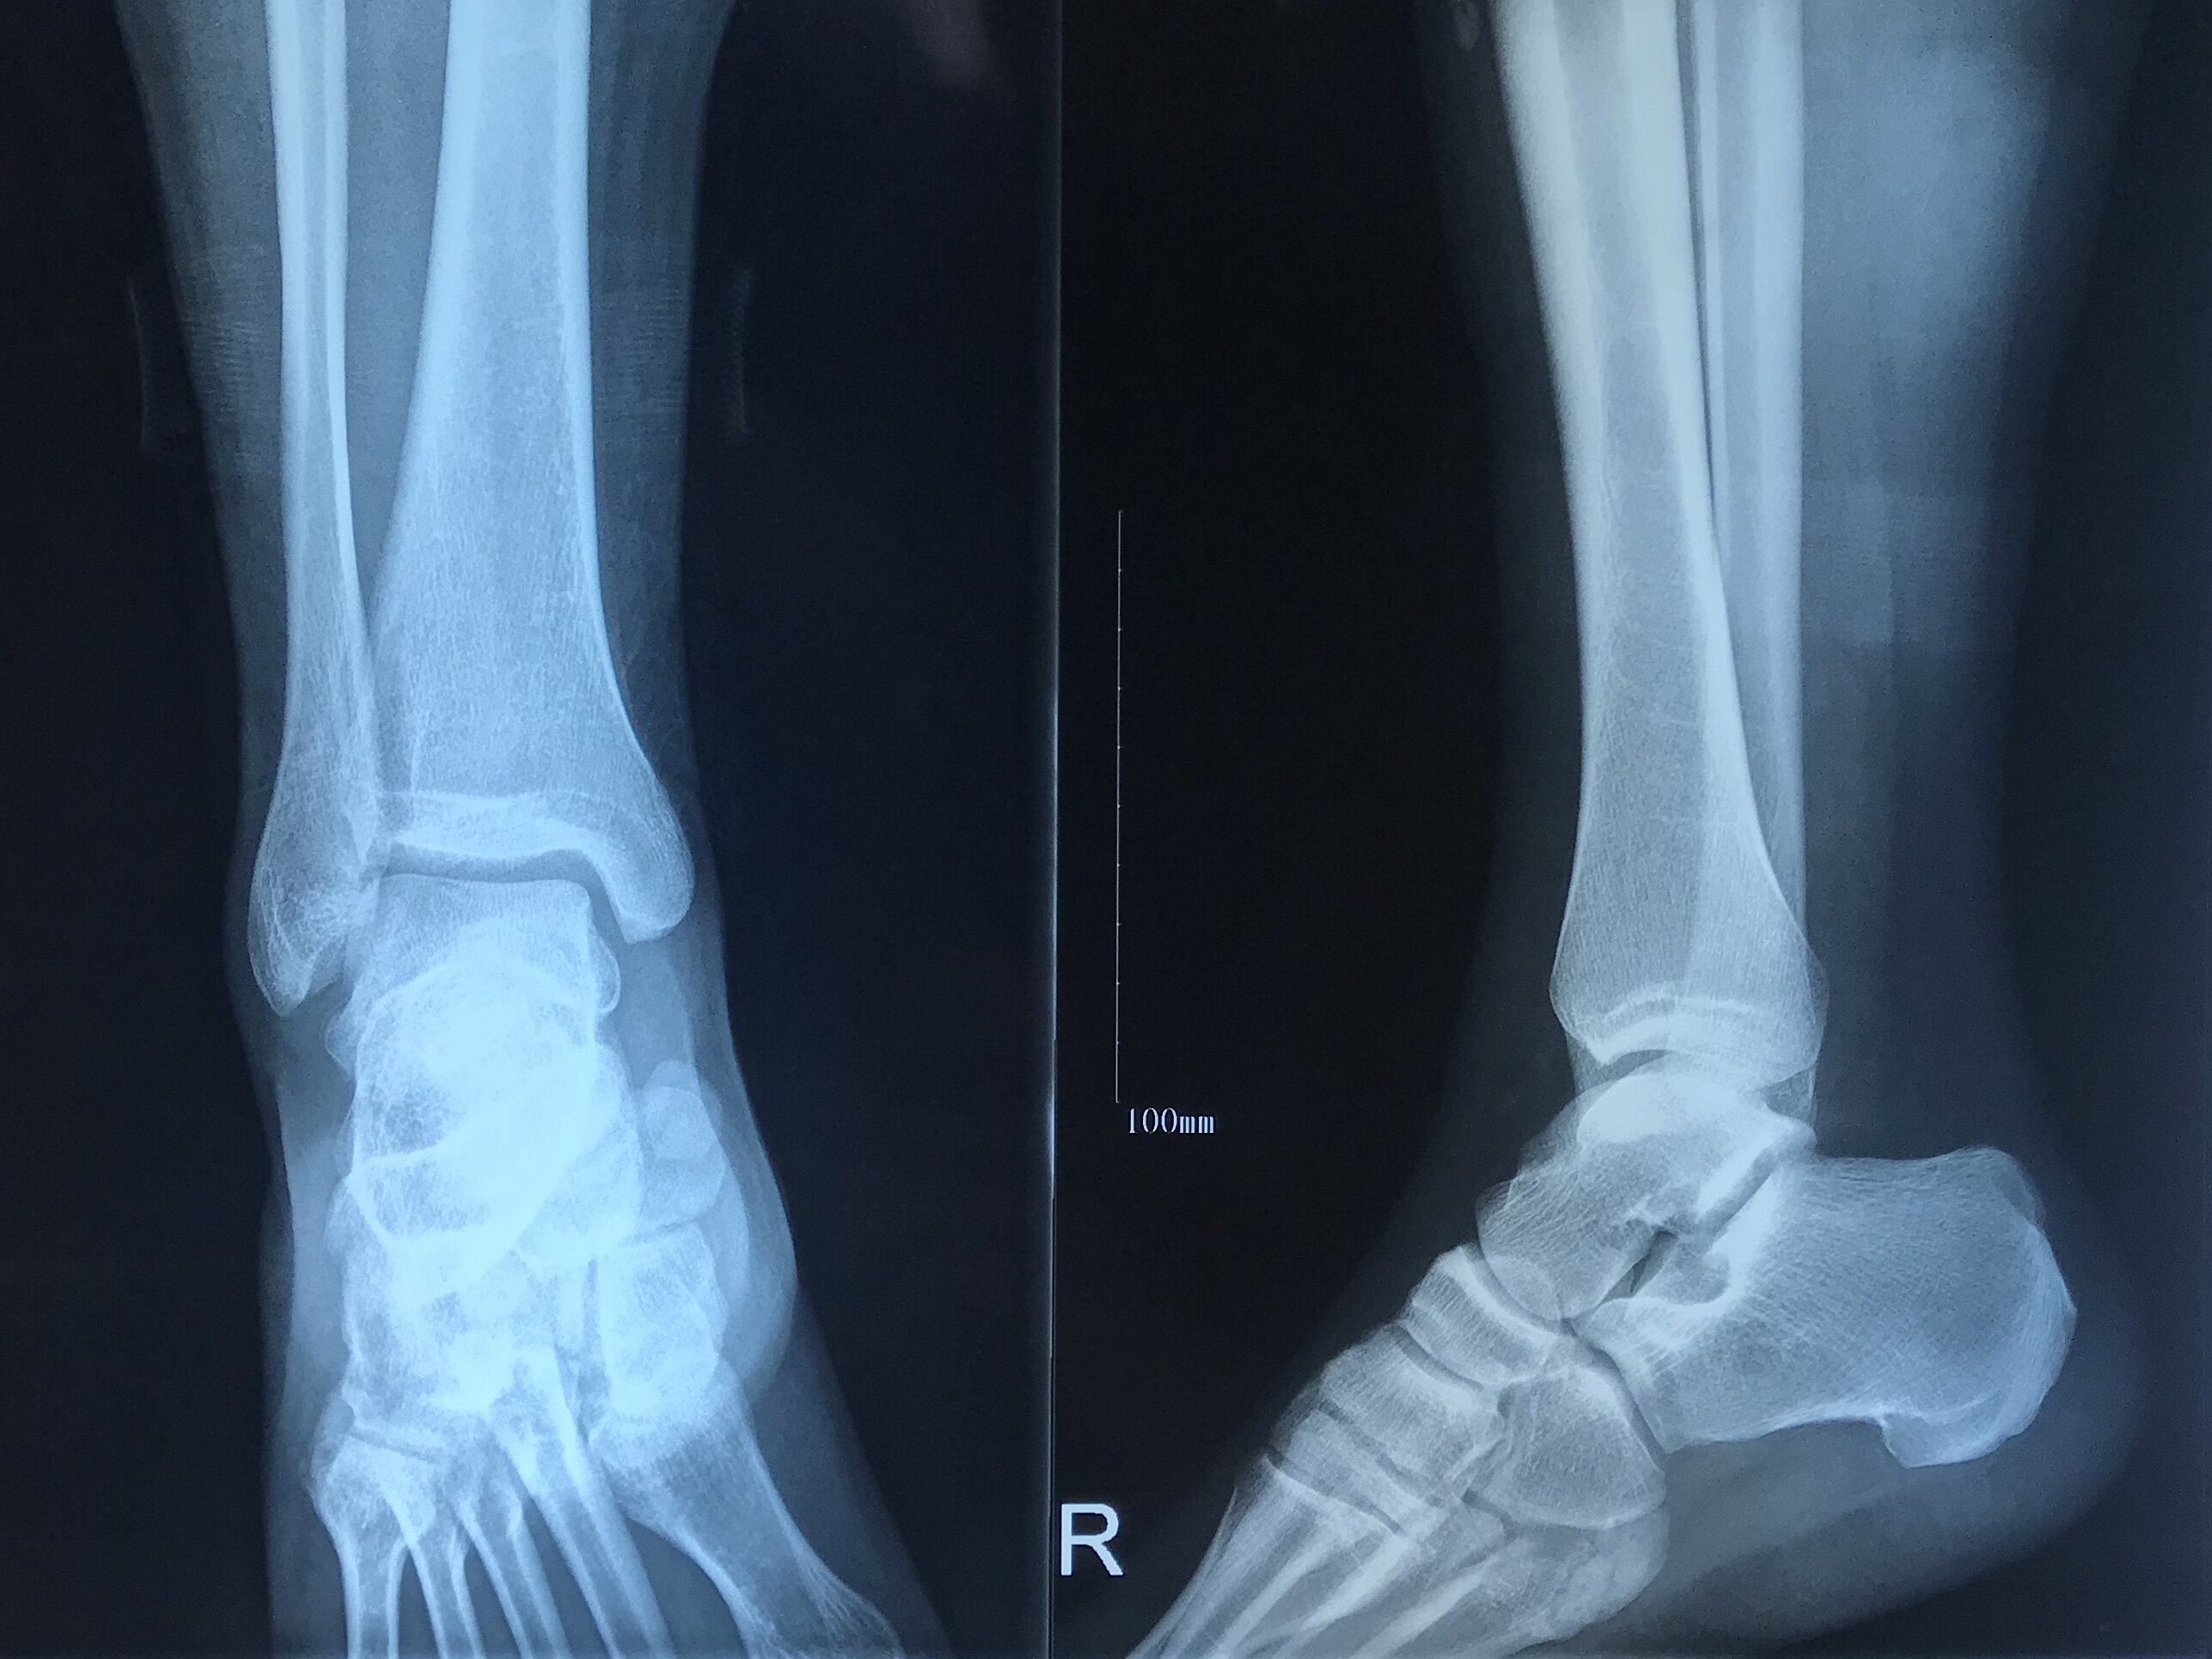

出車禍後 腳踝骨折第一次回診 Goodlucky23的部落格 痞客邦